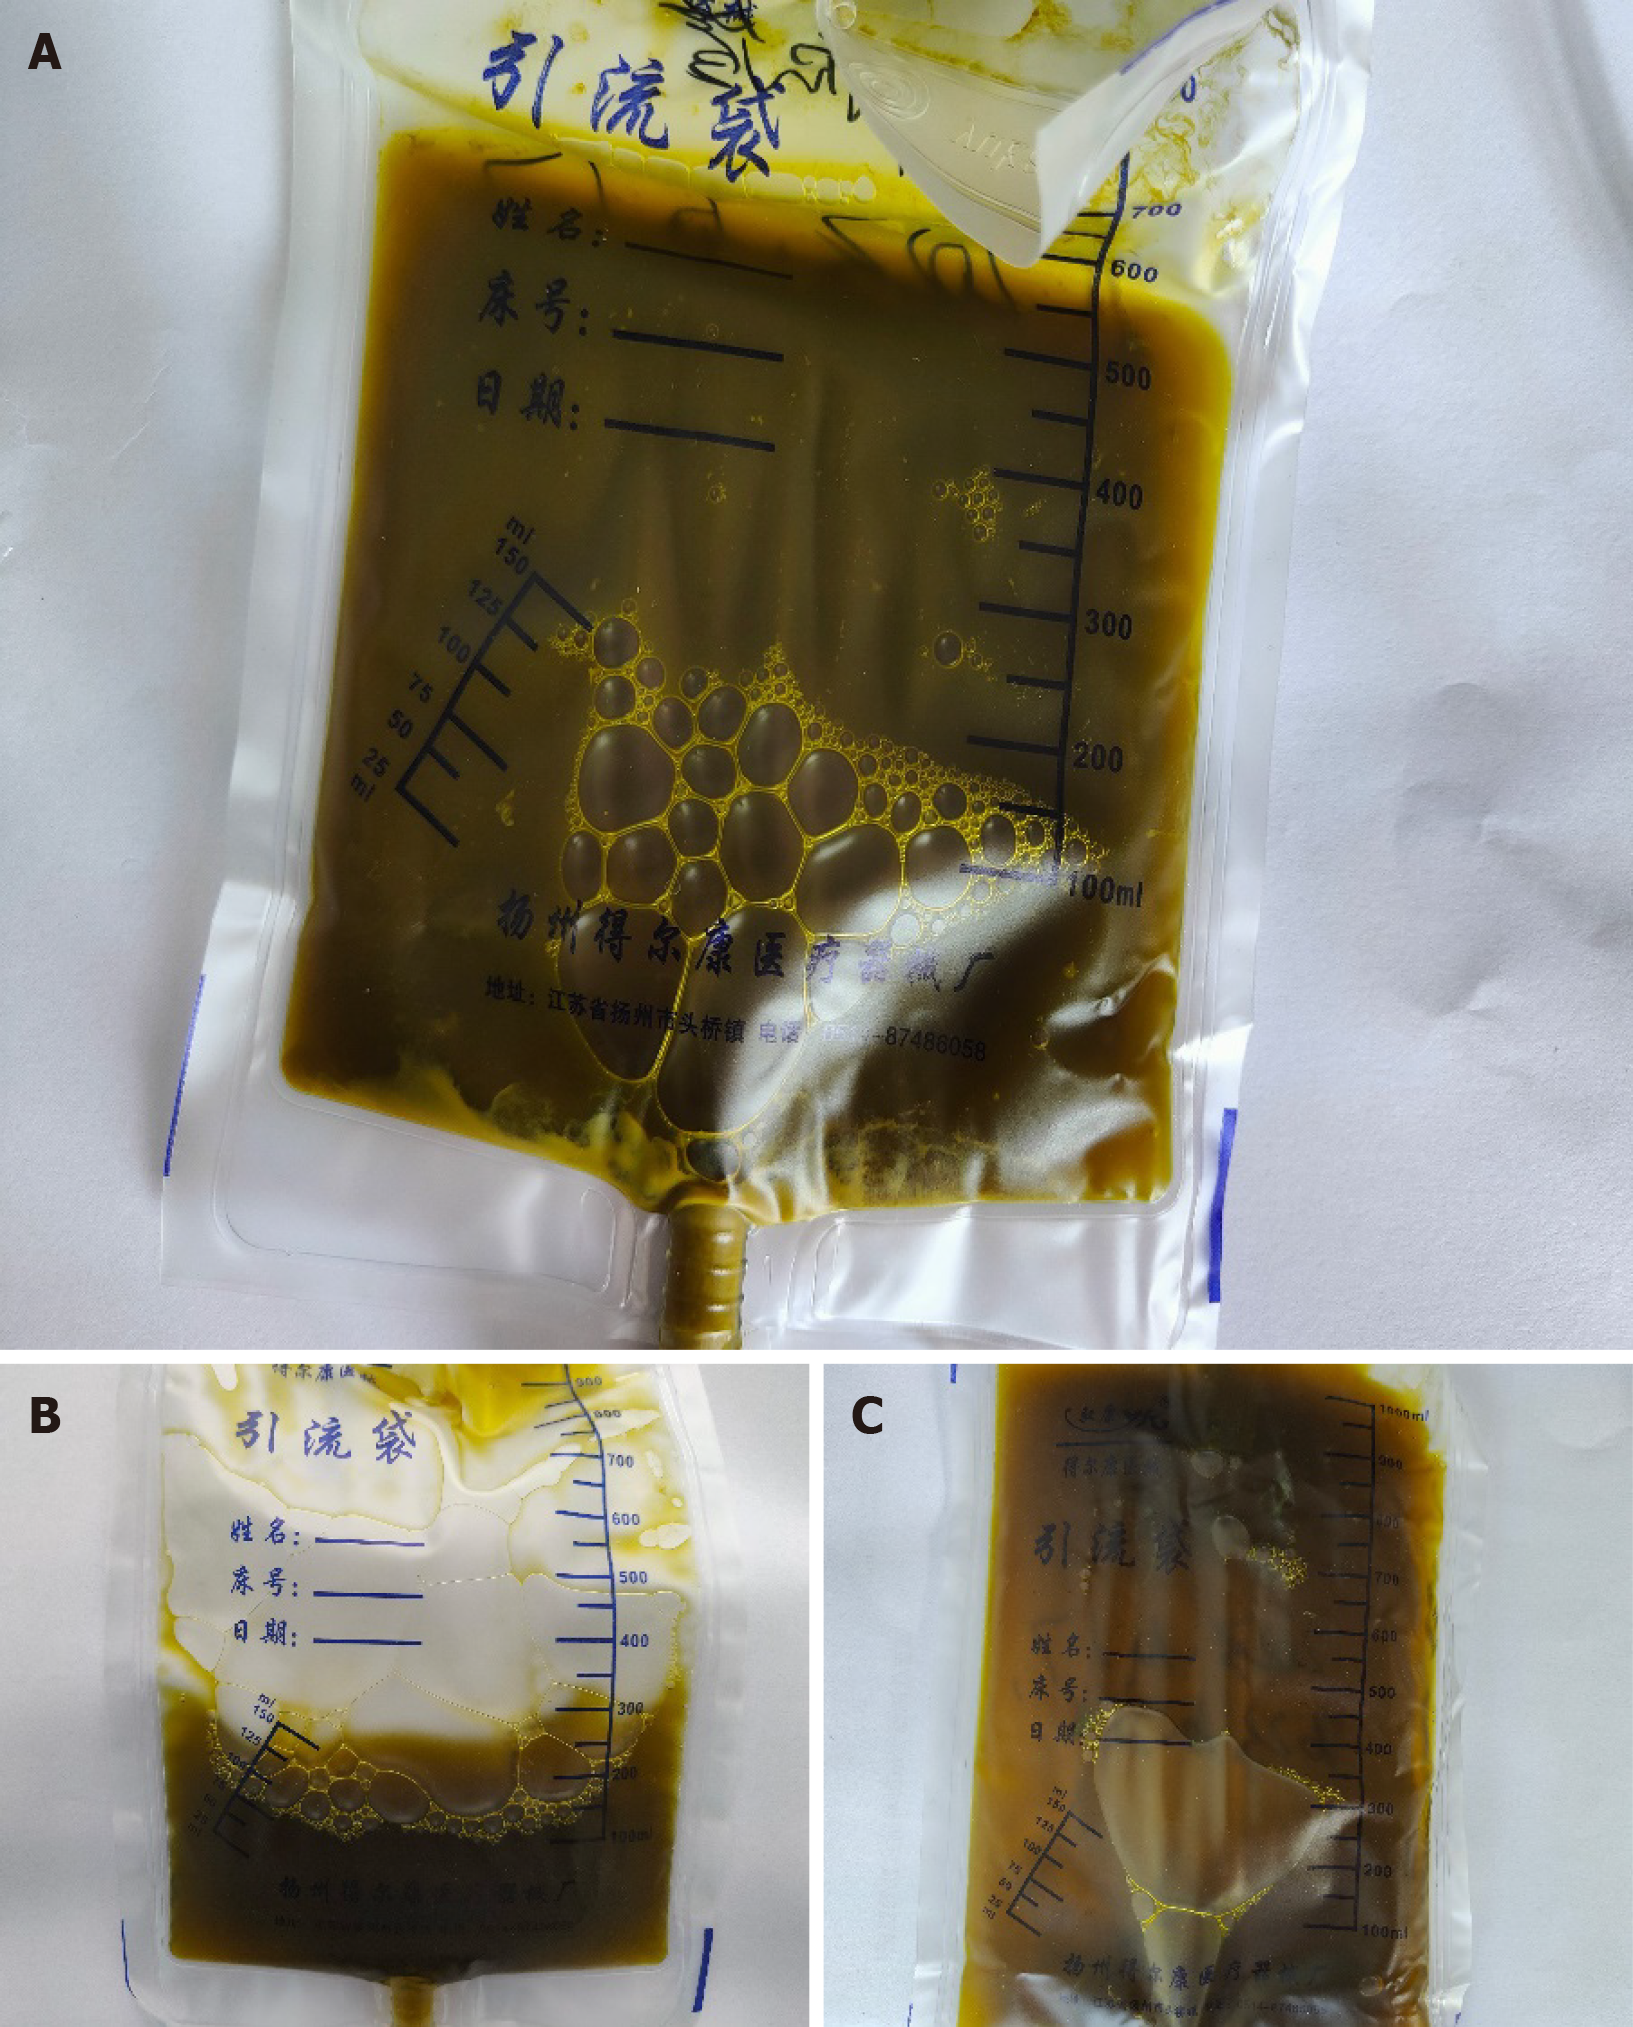

On the third day following admission, the patient developed high-grade fever (38.6 °C) presenting with chills. Consequently, cefoperazone sulbactam and dexamethasone were immediately administered to achieve fever control, and blood cultures were conducted. The culture confirmed bacteremia caused by Escherichia coli. Considering the diagnosis of acute cholangitis, PTCD was prioritized to decompress the biliary system and alleviate symptoms. During this procedure, we collected a yellow-green bile-stained fluid on the same day (Figure 3). Laboratory findings demonstrated elevated body temperature, abnormal complete blood count, and increased production of inflammatory markers (Table 2). The patient was put on empiric antibiotics therapy, which was later adjusted to imipenem and cilastatin sodium based on culture sensitivity. Once clinical stabilization was achieved, the patient was discharged with an indwelling drainage catheter for continued decompression.